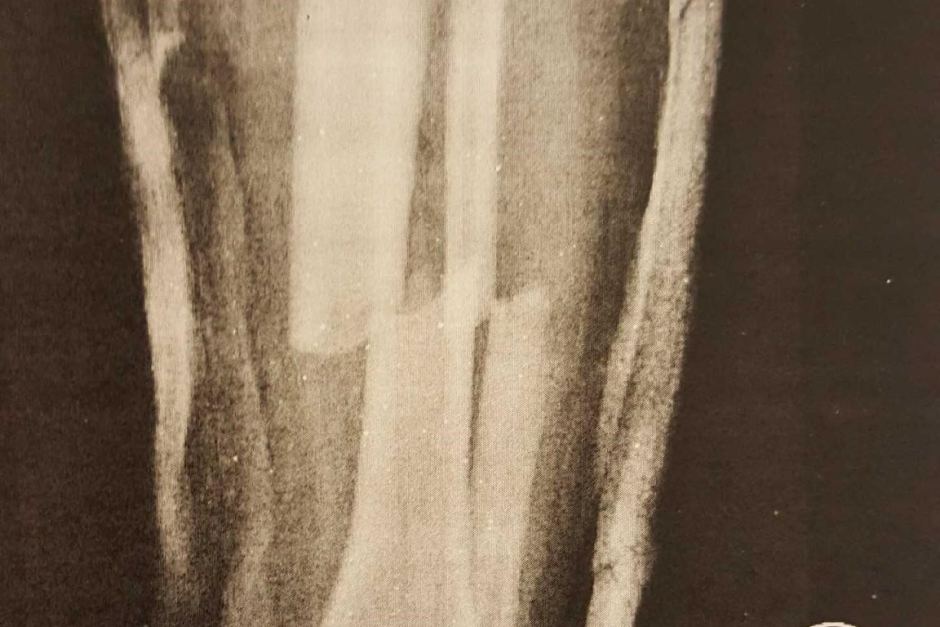

Adam Bart, 16, was with his family at a trampoline centre when he broke his leg in two places.

His mother Simonne Bax said Adam was attempting a trick when he fell awkwardly.

“He’d actually gone through the skin with his bones,” she said. “Blood started to pool out. He started to get the shakes.

“I could hear him screaming the whole way from the waiting area.”

It took two paramedic crews and a cocktail of strong painkillers to get Adam into an ambulance.

Emergency surgery resulted in a steel rod and four screws in his leg. He spent the next four months recovering.

Complications from the surgery affected his liver and he will need the rod in his leg replaced as he gets older.

“The doctors said that because of the velocity, it’s like what you would see in a car crash,” Ms Bax said.